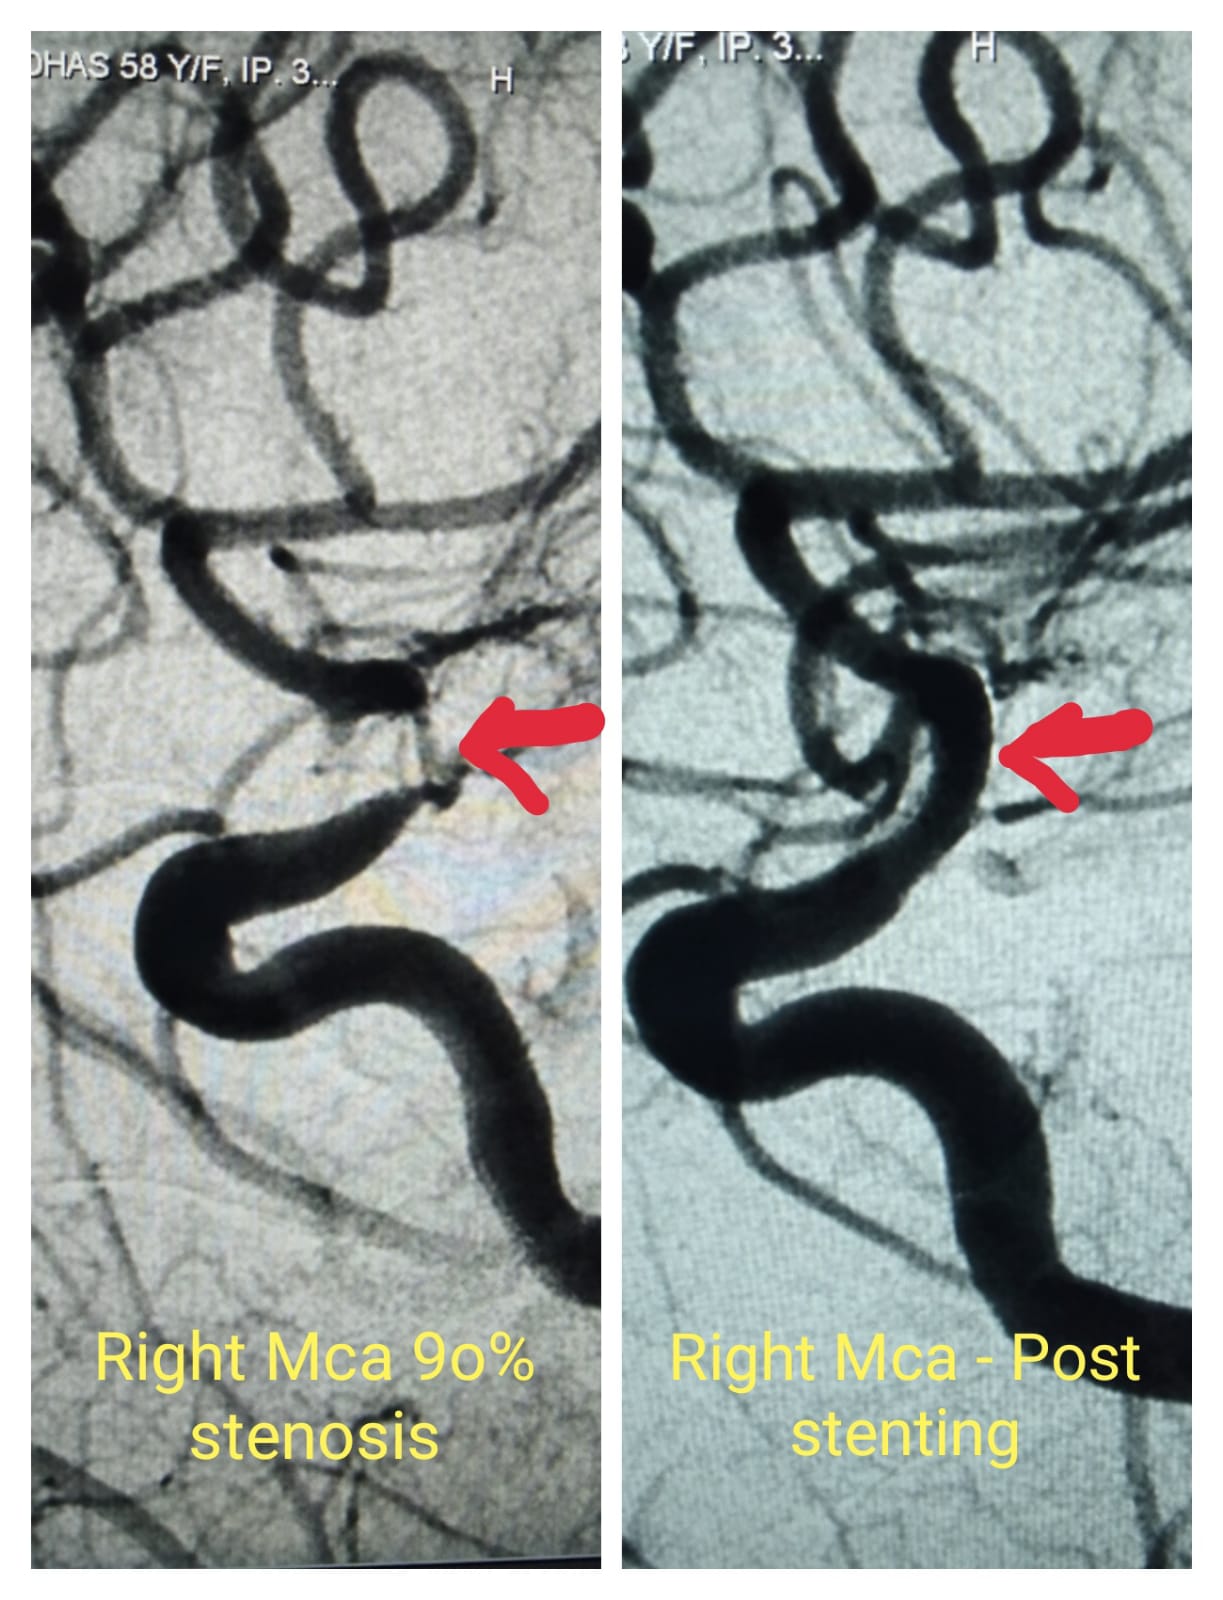

Cerebral Artery Stenting